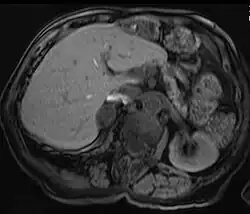

MRI scan T1 with fat saturation - adrenal adenoma

Adrenal adenomas are common, and are often found on the abdomen, usually not as the focus of investigation; they are usually incidental findings. About one in 10,000 is malignant. Thus, a biopsy is rarely called for, especially if the lesion is homogeneous and smaller than 3 centimeters. Follow-up images in three to six months can confirm the stability of the growth.

While some adrenal adenomas do not secrete hormones at all, often some secrete cortisol, causing Cushing's syndrome, aldosterone causing Conn's syndrome, or androgens causing hyperandrogenism.